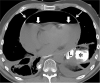

An esophagopericardial fistula is a rare complication of esophageal malignancy, trauma, or surgery. Imaging is a cornerstone of diagnosis, with detection of pneumopericardium or hydropneumopericardium at imaging raising suspicion for pyopneumopericardium and prompting immediate search for the causative pathologic process. Given the high associated mortality rate of over 50% for patients with esophagopericardial fistulas, early diagnosis and intervention are vital. Supplemental material is available for this article. © RSNA, 2020.